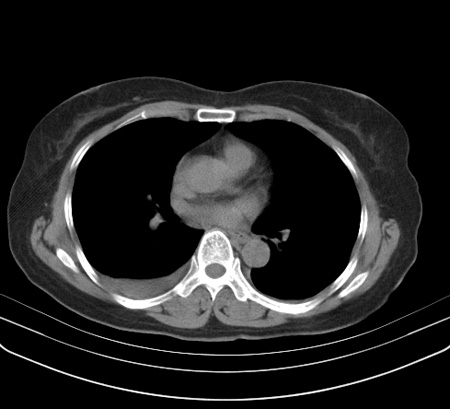

以下是引用余辉在2009-2-19 20:10:00的发言:[br]多考虑急性感染性病变,右中叶尚可见多枚小斑片状影,多为化脓性肺炎,双侧胸腔积液

以下是引用随光逐影在2009-2-19 20:33:00的发言:[br]1)考虑右肺炎症;建议抗炎治疗后复查。2)双侧胸腔积液(以右侧为甚)。

以下是引用花凤凰在2009-2-19 20:46:00的发言:[br]病人有发热,胸痛急性起病,主要病变位于右肺中叶外侧段,呈楔行改变,位于外带胸膜下,考虑为肺梗塞可能!!!!!!!!!!!!!!!!!!!!!!!!!!!!!!!!!!!